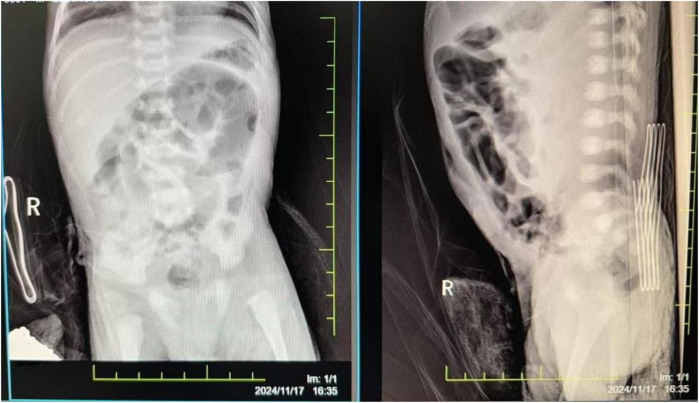

严重的新生儿窒息可导致多器官功能障碍综合征(MODS),并增加死亡和残疾风险。本病例报告描述了一个经历了15分钟严重窒息的新生儿的成功复苏和管理。男婴在妊娠36周时通过紧急剖宫产出生,Apgar评分极低(1分,5分和10分)。他接受了15分钟的复苏,包括气道清理、气管插管、正压通气、胸外按压和多次肾上腺素治疗。复苏后,他表现出严重的多器官功能障碍。婴儿接受了综合治疗,包括有创机械通气,急性肾损伤的持续肾替代治疗(CRRT),神经保护的治疗性低温,坏死性小肠结肠炎穿孔的手术治疗,以及专门的营养支持。他的病情明显改善,MODS得到缓解,出院时体重增加,进食耐受性良好。出院时的神经学评估未见明显异常;然而,长期随访正在进行中,以监测潜在的神经发育结果。本病例强调了及时复苏和细致的系统管理对于实现严重窒息和MODS新生儿良好预后的重要性。多学科团队的成功合作对新生儿的康复起了关键作用。

Severe neonatal asphyxia can lead to multiple organ dysfunction syndrome (MODS) and increase mortality and disability risks. This case report describes the successful resuscitation and management of a neonate who experienced 15 min of severe asphyxia. The male infant, born at 36 weeks' gestation via emergency cesarean section, had extremely low Apgar scores (1 at 1, 5, and 10 min). He underwent 15 min of resuscitation, including airway clearance, endotracheal intubation, positive pressure ventilation, chest compressions, and multiple administrations of epinephrine. Post-resuscitation, he exhibited severe dysfunction in multiple organ systems. The infant received comprehensive treatment, including invasive mechanical ventilation, continuous renal replacement therapy (CRRT) for acute kidney injury, therapeutic hypothermia for neuroprotection, surgical treatment for necrotizing enterocolitis with perforation, and specialized nutritional support. His condition significantly improved, with resolution of MODS, and he was discharged with weight gain and good feeding tolerance. Neurological assessments at discharge showed no significant abnormalities; however, long-term follow-up is ongoing to monitor for potential neurodevelopmental outcomes. This case highlights the importance of timely resuscitation and meticulous systemic management in achieving a favorable prognosis for neonates with severe asphyxia and MODS. The successful collaboration of a multidisciplinary team played a key role in the neonate's recovery.